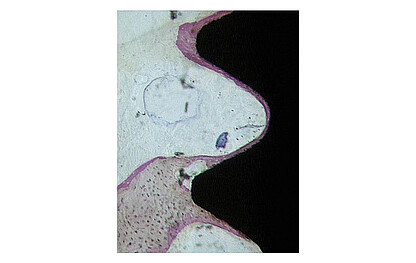

All implant systems in the BEGO Semados® product range feature the proven TiPurePlus surface, with the exception of the provisional PI-Line. This entails sandblasting and etching the implant blank, which is made of Grade 4 commercially pure titanium, using a special, precisely defined technology.

The purity of this surface sets new standards [1]. Surface residues from the blasting and etching process are not detectable. Moreover, the homogeneous surface has a very high protein-binding capacity, which has a positive effect on the healing time of implants.